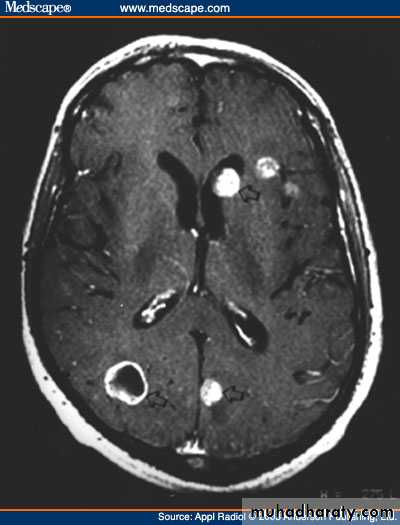

Brain metastasis

• Metastases in the brain may be of high, iso, or low density

• They usually show contrast enhancement (ring enhancement(

• They are often surrounded by significant oedema

• Metastases are typically multiple.

• A solitary metastasis is indistinguishable from a primary intracerebral brain tumour.